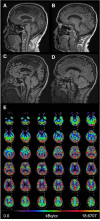

Case presentation: Herein we present a case of a 62-year-old man who developed a subacute cerebellar syndrome with limb-, truncal- and gait ataxia and scanning speech 1 day after clinical resolution of symptomatic SARS-CoV-2 infection of the upper airways. Apart from ataxia, there were no signs indicative of opsoclonus myoclonus ataxia syndrome or Miller Fisher syndrome. Cerebral magnetic resonance imaging showed mild cerebellar atrophy. SARS-CoV-2 infection of the cerebellum was excluded by normal cerebrospinal fluid cell counts and, most importantly, absence of SARS-CoV-2 RNA or intrathecal SARS-CoV-2-specific antibody production. Other causes of ataxia such as other viral infections, other autoimmune and/or paraneoplastic diseases or intoxication were ruled out. The neurological deficits improved rapidly after high-dose methylprednisolone therapy.